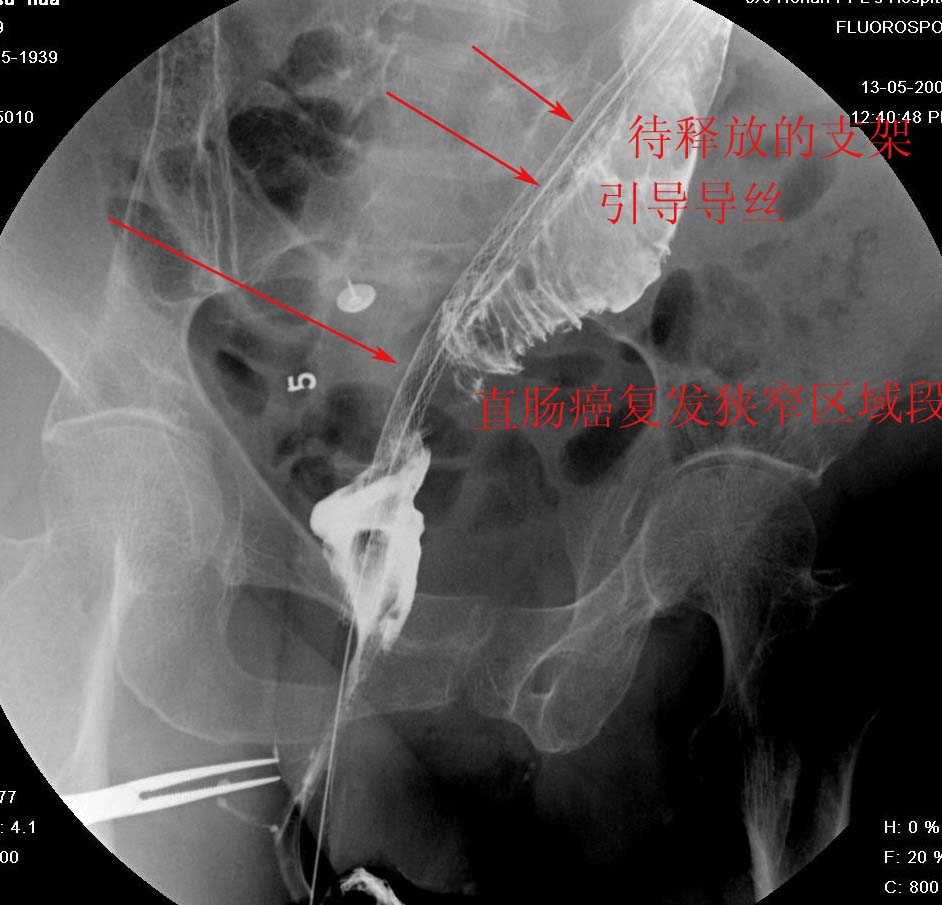

直肠癌术后两年.经过检查发现肝和腹膜后均出现转移情况,申请介入治疗.介入治疗情形见下图: